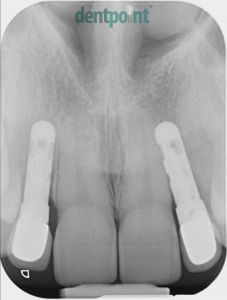

Régi implantátumok cseréje, fémmentes koronák felhelyezése

Fiatal hölgy páciensünk a 10 évvel ezelőtt behelyezett implantátumainak csontpusztulása és ínyének visszahúzódása miatt keresett fel minket. A régi implantátumok eltávolítását követően újakat helyeztünk be, és ínyplasztikai kezeléssel, valamint cirkónium egyéni implantátum fejekre készített e.max fémmentes kerámia koronákkal adtuk vissza páciensünk elégedett mosolyát.

1) Kiindulási helyzet röntgenfelvétel

2) Implantátumcsere utáni röntgenfelvétel